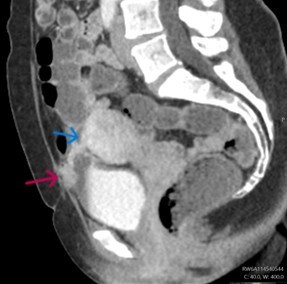

A contrast-enhanced CT scan (Figures 1 & 2) revealed a bladder tethered to the uterus with a diverticulum exhibiting irregular wall thickening and enhancement along its anterior-superior aspect. Subsequently, a 0.5 g bladder tissue, including the lesional area was resected during TURBT procedure. Her past medical history includes three caesarean sections, one complicated by an incidental bladder injury. She denies smoking, occupational chemical exposure, pelvic radiotherapy, chronic catheter use, anticoagulant therapy, nephrolithiasis apart from the noted calculus, recurrent gross haematuria outside infection or systemic diseases and there is no family history of urological malignancy.

Radiological findings are often nonspecific, making pre-operative diagnosis challenging. Histological examination is essential for confirmation. It reveals tubal or papillary structures lined by characteristic fallopian tube-type epithelium with three types of cells, which include ciliated cells, mucinous cells, and intercalated cells, located in the lamina propria or muscularis propria of the urinary bladder wall. Immunohistochemistry findings are identical to the fallopian tube with CK7, oestrogen, and progesterone receptor positivity and absence of urothelial markers like GATA3, uroplakin II, uroplakin III and P63.